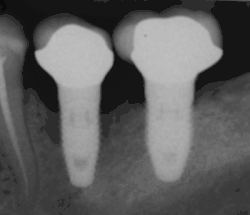

Die Diagnostik der Periimplantitis erfolgt in zwei Schritten. Zunächst erfolgt die klinische Diagnostik durch Sondierung des periimplantären Bereichs mittels Parodontalsonden. Eine auftretende Blutung, die auch von einer Eiterentleerung begleitet sein kann, führt zur Verdachtsdiagnose der Periimplantitis, die anschließend mittels Röntgenaufnahmen, bevorzugt durch intraorale Zahnfilmaufnahmen, von einer reinen Mukositis differentialdiagnostisch abgegrenzt beziehungsweise bestätigt werden kann. Die Mukositis verläuft suprakrestal, also oberhalb des Knochensaums. Die Defektklassifizierung erfolgt nach Schwarz et al.[6]